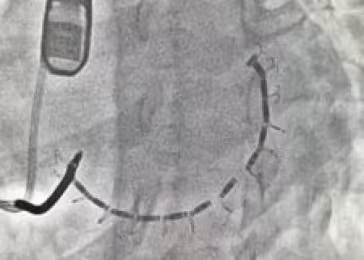

Paul Sorajja, MD, a global leader in structural heart disease interventions and research, is also on the team. He performed a minimally invasive procedure called transcatheter mitral valve repair (TMVR) to help repair Joni’s mitral valve. Dr. Sorajja’s research at MHIF has directly contributed to the advance in treatments available for the mitral valve, which acts as a door that separates the left atrium from the left ventricle and keeps blood from regurgitating or flowing backward. Dr. Sorajja gave Joni a Mitra Clip to help her mitral valve decrease regurgitation.

"That mitral valve clip was beneficial for me," added Joni. "It went from severe to trace regurgitation right after the surgery."